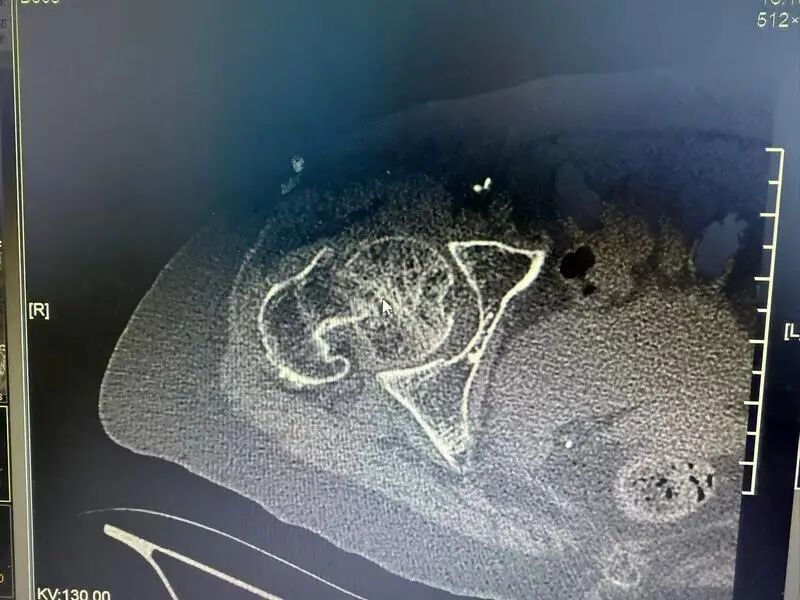

冬季是老年人骨折的高发时期。近日,90岁的张阿婆在家中不慎摔倒,导致髋关节骨折,被送往仁济医院宝山分院骨科接受手术治疗。术后恢复良好,即将出院,实现了快速康复。据悉,12月以来,该科室已连续收治9例类似高龄骨折患者。 张阿婆回忆,摔倒时自己正在正常行走,突然失去平衡跌坐在地,无法起身。经检查,她被诊断为左侧股骨颈骨折。尽管平日没有严重基础疾病,但检查显示其心脏已出现老化性改变,且当时伴有肺部感染,这些因素都可能诱发意外。 医生指出,老年人冬季活动减少,容易发生呼吸道感染,导致身体机能下降,出现头晕、乏力等症状,从而增加跌倒风险。“这种髋部骨折在老年群体中较为常见,因长期卧床可能引发严重并发症,甚至危及生命,因此常被称为‘人生最后一次骨折’。” 手术前 手术后 考虑到张阿婆年事已高,并伴有心肺功能减退和肺部感染,医院骨科团队迅速组织心内科、麻醉科、呼吸科等多学科会诊,经全面评估后,确定了“尽早手术、尽快恢复活动”的治疗方案。术后3—5天,老人就可以下床活动,逐步恢复日常生活状态。 医生提醒,冬季是老人摔倒骨折的高危季节。老年人反应能力相对下降,起夜时意识不清或视线不佳,室内地面湿滑、障碍物多,以及冬季心脑血管疾病易发等因素,均会增加摔倒风险。 为有效预防,家庭应重视适老化改造,例如减少地面高低差、保持通道畅通、在卫生间加装防滑垫和扶手;保持室内温度适宜,避免衣物过于厚重;雨雪天气尽量减少外出。同时,应关注骨质疏松的防治,在医生指导下科学补钙并进行抗骨质疏松治疗。 “建议适当开窗通风,预防呼吸道感染导致老年人心肺系统功能下降;天气晴好时增加户外活动,适度晒太阳、锻炼,增强骨骼和肌肉健康。”医生补充道,“如老人行动已显不便,可根据情况配备拐杖、助行器或轮椅。一旦出现不适,应及时就医,把握治疗黄金期。” 对于已发生髋部骨折的老年患者,医生强调,在身体状况允许的前提下,应尽早接受手术评估与治疗。目前,微创手术与快速康复理念的推广,已使更多高龄患者有机会摆脱“人生最后一次骨折”的威胁,重新获得自主活动能力。